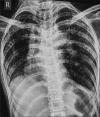

Hermansky-Pudlak syndrome (HPS) is an extremely subtile autosomal recessive disorder characterized by tyrosinase-positive oculocutaneous albinism (Ty-pos OCA), bleeding tendencies, and systemic complications associated to lysosomal dysfunction. The most grave complication of disease is interstitial lung disease (ILD) leading to irrevocable pulmonary fibrosis. Patients with HPS-1, HPS-2, and HPS-4 variants have a penchant to develop pulmonary fibrosis. The pulmonary involvement is characterised by progressive dyspnea hypoxemia respiratory failure and corpulmonale. The disease has an unfortunate prognosis with a high mortality rate and a poor quality of life. The options currently available in the therapeutic armamentarium are dismal with a dire need for opportune research. We hereby narrate an intriguing case scenario of a pair of siblings affected with this rare disorder with its associated ILD.